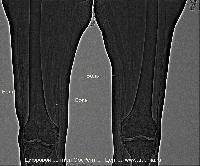

Магнитно-резонансная томография (МРТ):один из самых эффективных методов диагностики заболеваний

В случае перелома шейки бедра компания МосРентген Центр госпитализирует в Склиф для эндопротезирования.